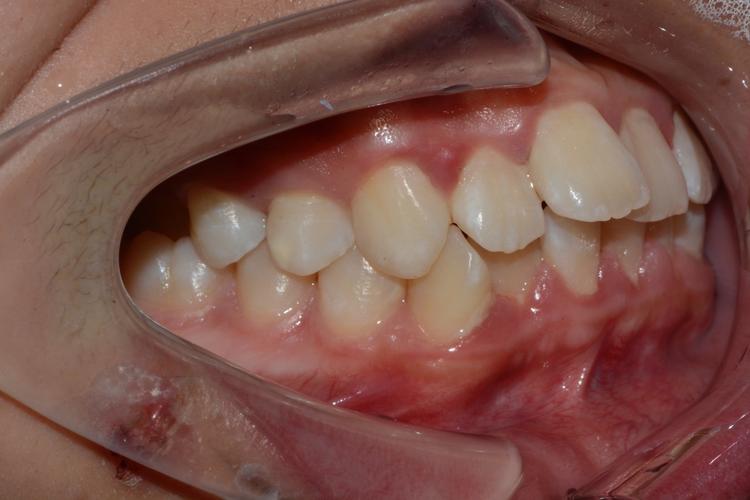

低位水平阻生齿的正畸治疗核心在于“解除阻生、引导萌出、保存功能”,通过科学设计牵引路径,将埋藏的牙齿移动至正常咬合位置,避免邻牙损害及颌骨破坏,治疗前需全面评估:临床检查需观察口腔黏膜状况、邻牙松动度及咬合关系;影像学检查是关键,通过CBCT可清晰显示阻生牙的萌出方向、牙根形态、与邻牙牙根及下颌神经管的距离,判断是否具备牵引条件;同时需研究模型分析咬合曲线,制定个性化方案。

当阻生牙牵引至正常咬合位置后,拆除矫治器,佩戴保持器(如Hawley保持器或透明保持器),防止牙齿复发移位,期间需定期复查(每3个月1次),监测牙周状况及咬合稳定性。